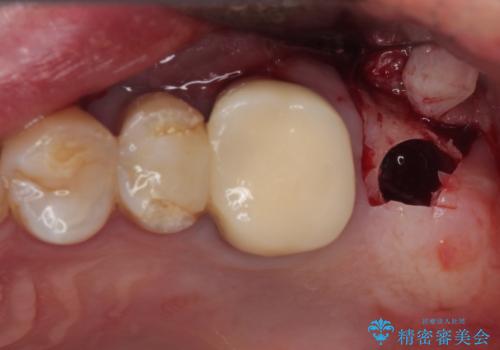

- 破損したクラウンと、奥歯の欠損を気にして来院された患者様です。

奥歯の欠損部はインプラントによる補綴治療を、手前の破損したクラウンは作り替えをご希望でした。

しかしながら、レントゲンやCT画像から、手前の破損したクラウンの根尖部に大きな病変が認められ、インプラント埋入部にまで病変が及んでいることから、まずは手前の根管治療を行い、病変の正体を確認した後にインプラント埋入を行うこととしました。

口があまり開かず、インプラントの埋入角度がやや斜めとなりましたが、機能的には全く問題なく治療を終えることができました。